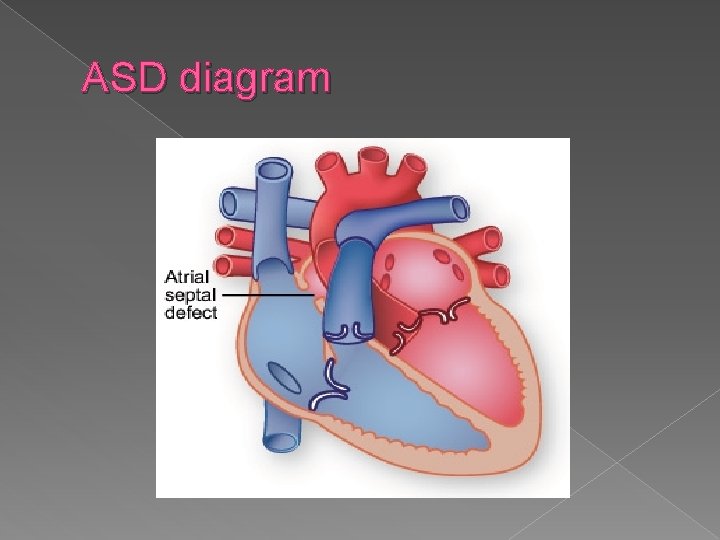

Structural Cardiac Anomalies Atrial Septal Defect (ASD) � Any abnormal opening between the atria is referred to as an atrial septal defect. ASDs are associated with a variety of cardiac and chromosomal abnormalities. Diagnosis is difficult because of the normal patent foramen ovale. Sonographic findings: � Relies on demonstration of echo dropout at the level of atrial septum � Since foramen ovale is normally open, prenatal diagnosis is unlikely.

ASD- Atrial septal defect Any abnormal opening between the atria is an ASD. Hard to diagnosis because of the normal patent foramen ovale.

ASD diagram